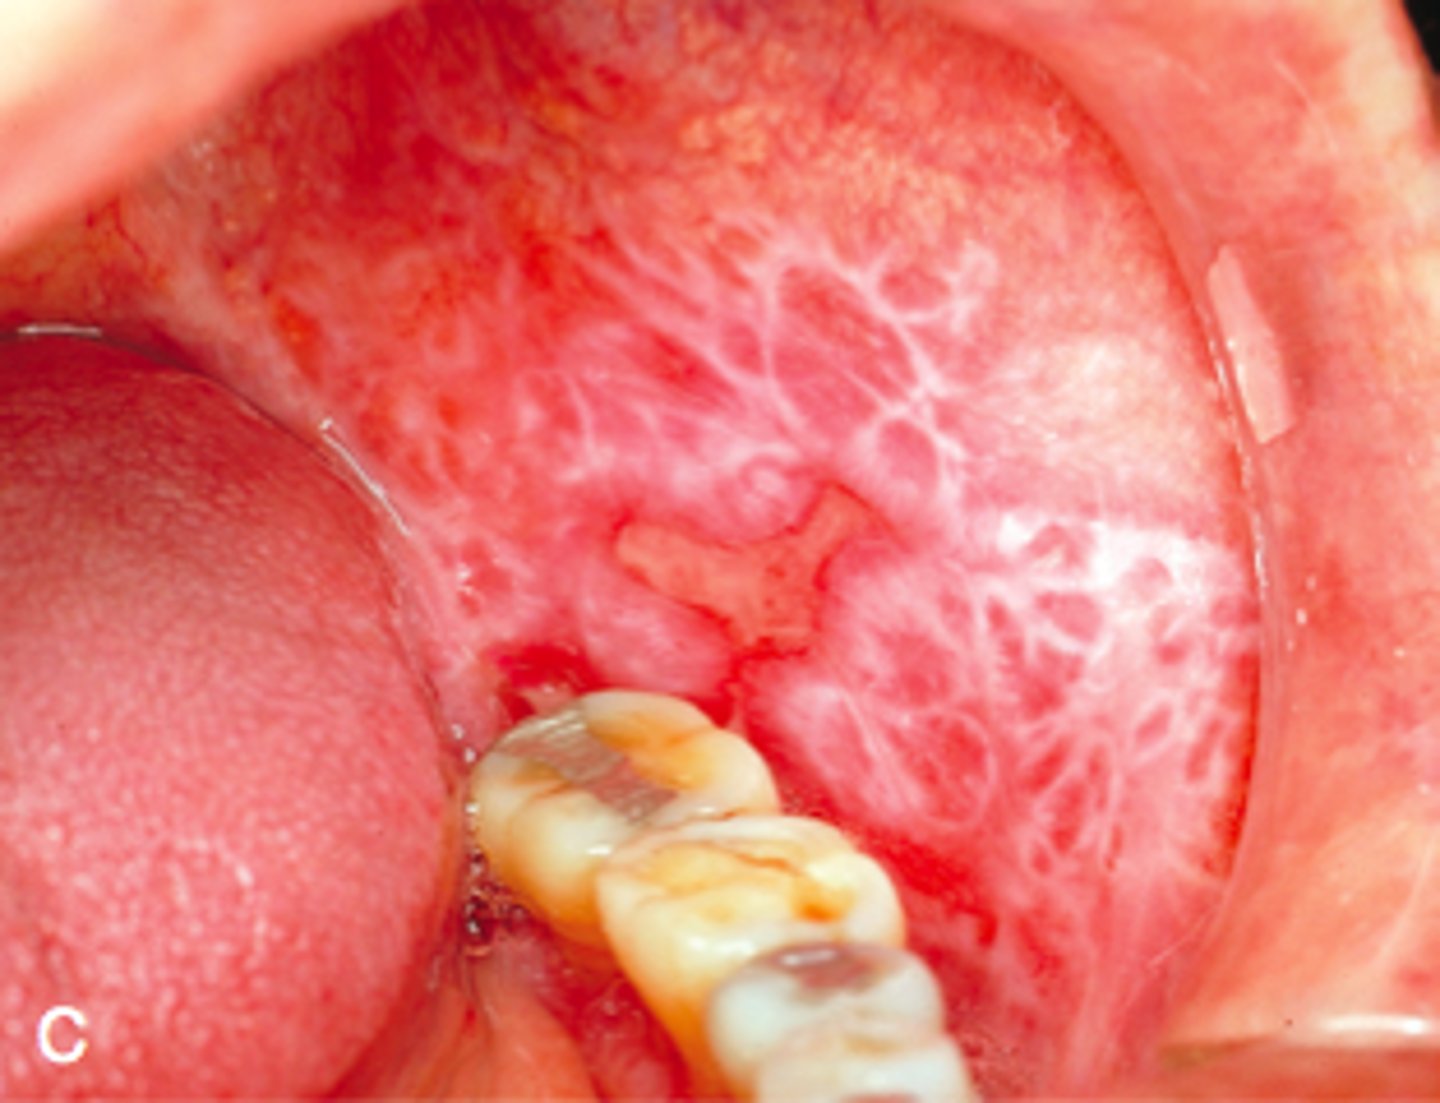

White lesion present on buccal mucosa. Likely diagnosis?

lichen planus

- white lesion can be describe as Wickham striae